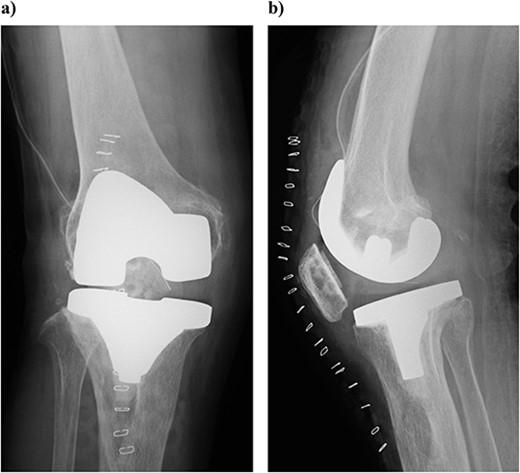

Plain radiography immediately after the surgery: (a) front and (b) lateral side. A slight dilation of the medial joint space is observed.

At 3 years postoperatively, the patient could walk independently. Her extension and flexion were − 5° and 120°, respectively, her KS score was 83 points, and her KS-F score was 90 points. Radiography showed a slight valgus position, with some lateral subluxation of the patella, but the patient reported no problems with her activities of daily living (Fig. 5).

Outcome at 3 years after surgery on plain radiography: (a) standing front and (b) side. The patella is laterally subluxated in a slight valgus position.